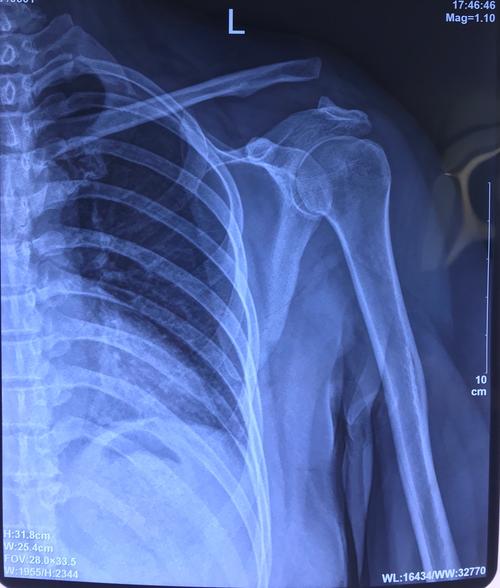

肩锁关节脱位三度图片

肩锁关节脱位三度图片,肩锁关节脱位二度图片

肩锁关节脱位

肩锁关节脱位术前术后

肩锁关节脱位图片

右肩锁关节脱位图片

肩锁关节脱位三度

肩锁关节脱位x线图片